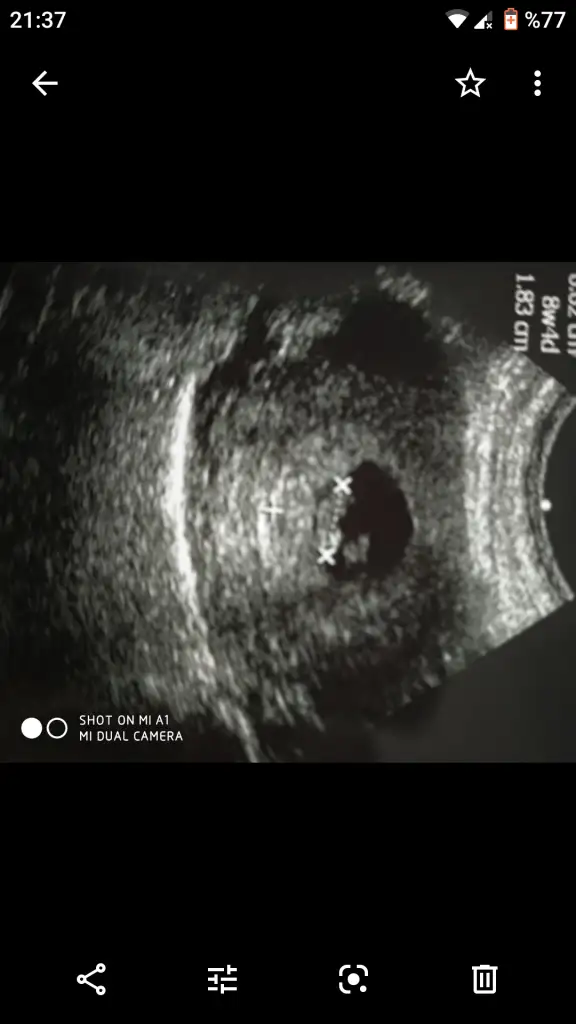

Arkadaşlar hamiş olan anne adaylarımıza hayırlı bir hamilelik dilerim. Bende 5 hafta 6 günlük hamileyim ilk kontrolüm gitmiş bulunmaktayım.Doktorum erkek bebek kesesine benziyor tabi hazırlık yapmayın sakın ha dedi. Bende konuyu araştırırken bu teoriye denk geldim yorumlarmısınız acaba.

ne demekmiş erkek bebek kesesi? Sordunuz mu nerden anladınız diye? Yuvarlak olması mı?